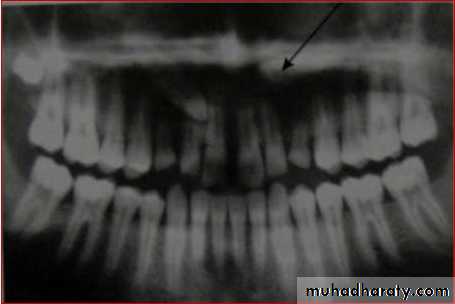

OPG

Panoramic radiographs are basic radiograph

for assessment of impacted teeth•

•

Tooth position whether deep or shallow

General orientation horizontal or inclined

mesially/distallyRelationship with neighbouring teeth

Risk of their transpositionPresence or absence of apical resorption of

roots of adjacent teeth

When mesio distal width of canine crown was

1.5 times larger (i.e. 15% larger) than theadjacent central incisor, then the canine is

palatally placed

This is only true in cases where canine should

not be at a higher level55

Ericson and Kurol in EJO 1988 defined number of

sectors to denote different types of impaction.

i.

ii.

Sector 1: if the cusp tip of the canine is

between the interincisor median line and the

long axis of the central incisor;

Sector 2: if the peak of the cuspid of the canine

is between the major axes of the lateral andcentral;

iii. Sector 3: if the peak of the cuspid of the canine

is between the major axis of the lateral and thefirst premolar.